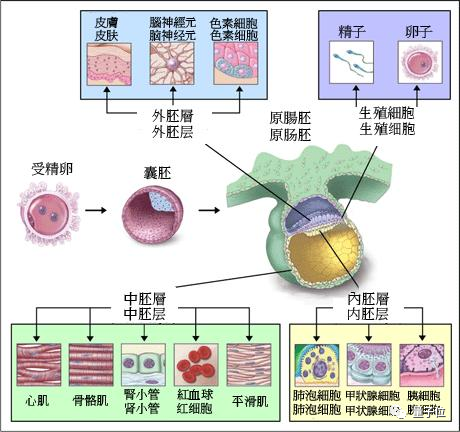

人类胚胎发育有三个过程,经过了受精卵、囊泡之后,就会变成原肠胚。

原肠胚它由三层细胞层构成:外胚层(ectoderm)、中胚层(mesoderm)、内胚层(endoderm)。

之后,各胚层继续伸长,形成前后端,随后进行分化,变成身体的各种组织部位。